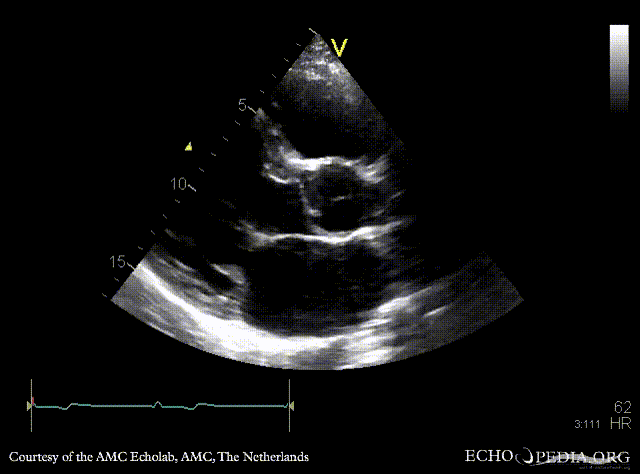

PSAX: redundant mitral valve leaflets